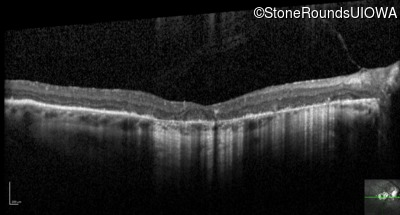

Optical Coherence Tomography - Right - 20/63

Exemplar / OCT Stack